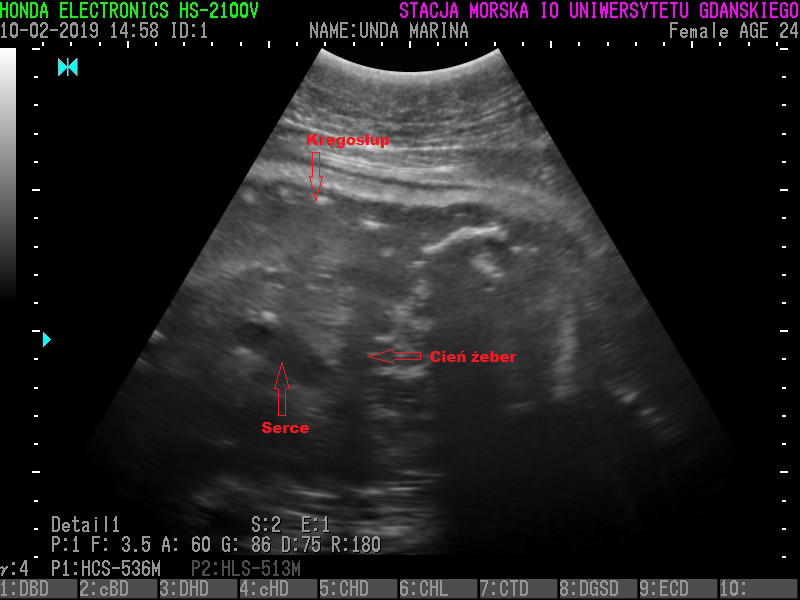

Za niespełna miesiąc helskie foki wydadzą na świat młode. Jak podaje fokarium, przyszłe focze mamy sukcesywnie przybierają na wadze, jedzą za dwoje i są coraz mniej mobilne. Stan zdrowia fok znajdujących się w heskim fokarium jest regularnie monitorowany, ze szczególnym uwzględnieniem ciężarnych samic: Ani, Undy i Ewy. Ostatnio odbyło się USG i ważenie przyszłych mam.

– One cały czas przybierają na masie, mają duży apetyt, dobrze się czują. Za mniej niż miesiąc wydadzą na świat młode. Będą to trzy foczki, gdyż każda samica może wydać na świat jedno młode – mówi Michał Bała ze Stacji Morskiej im. prof. Krzysztofa Skóry Instytutu Oceanografii Uniwersytetu Gdańskiego w Helu.